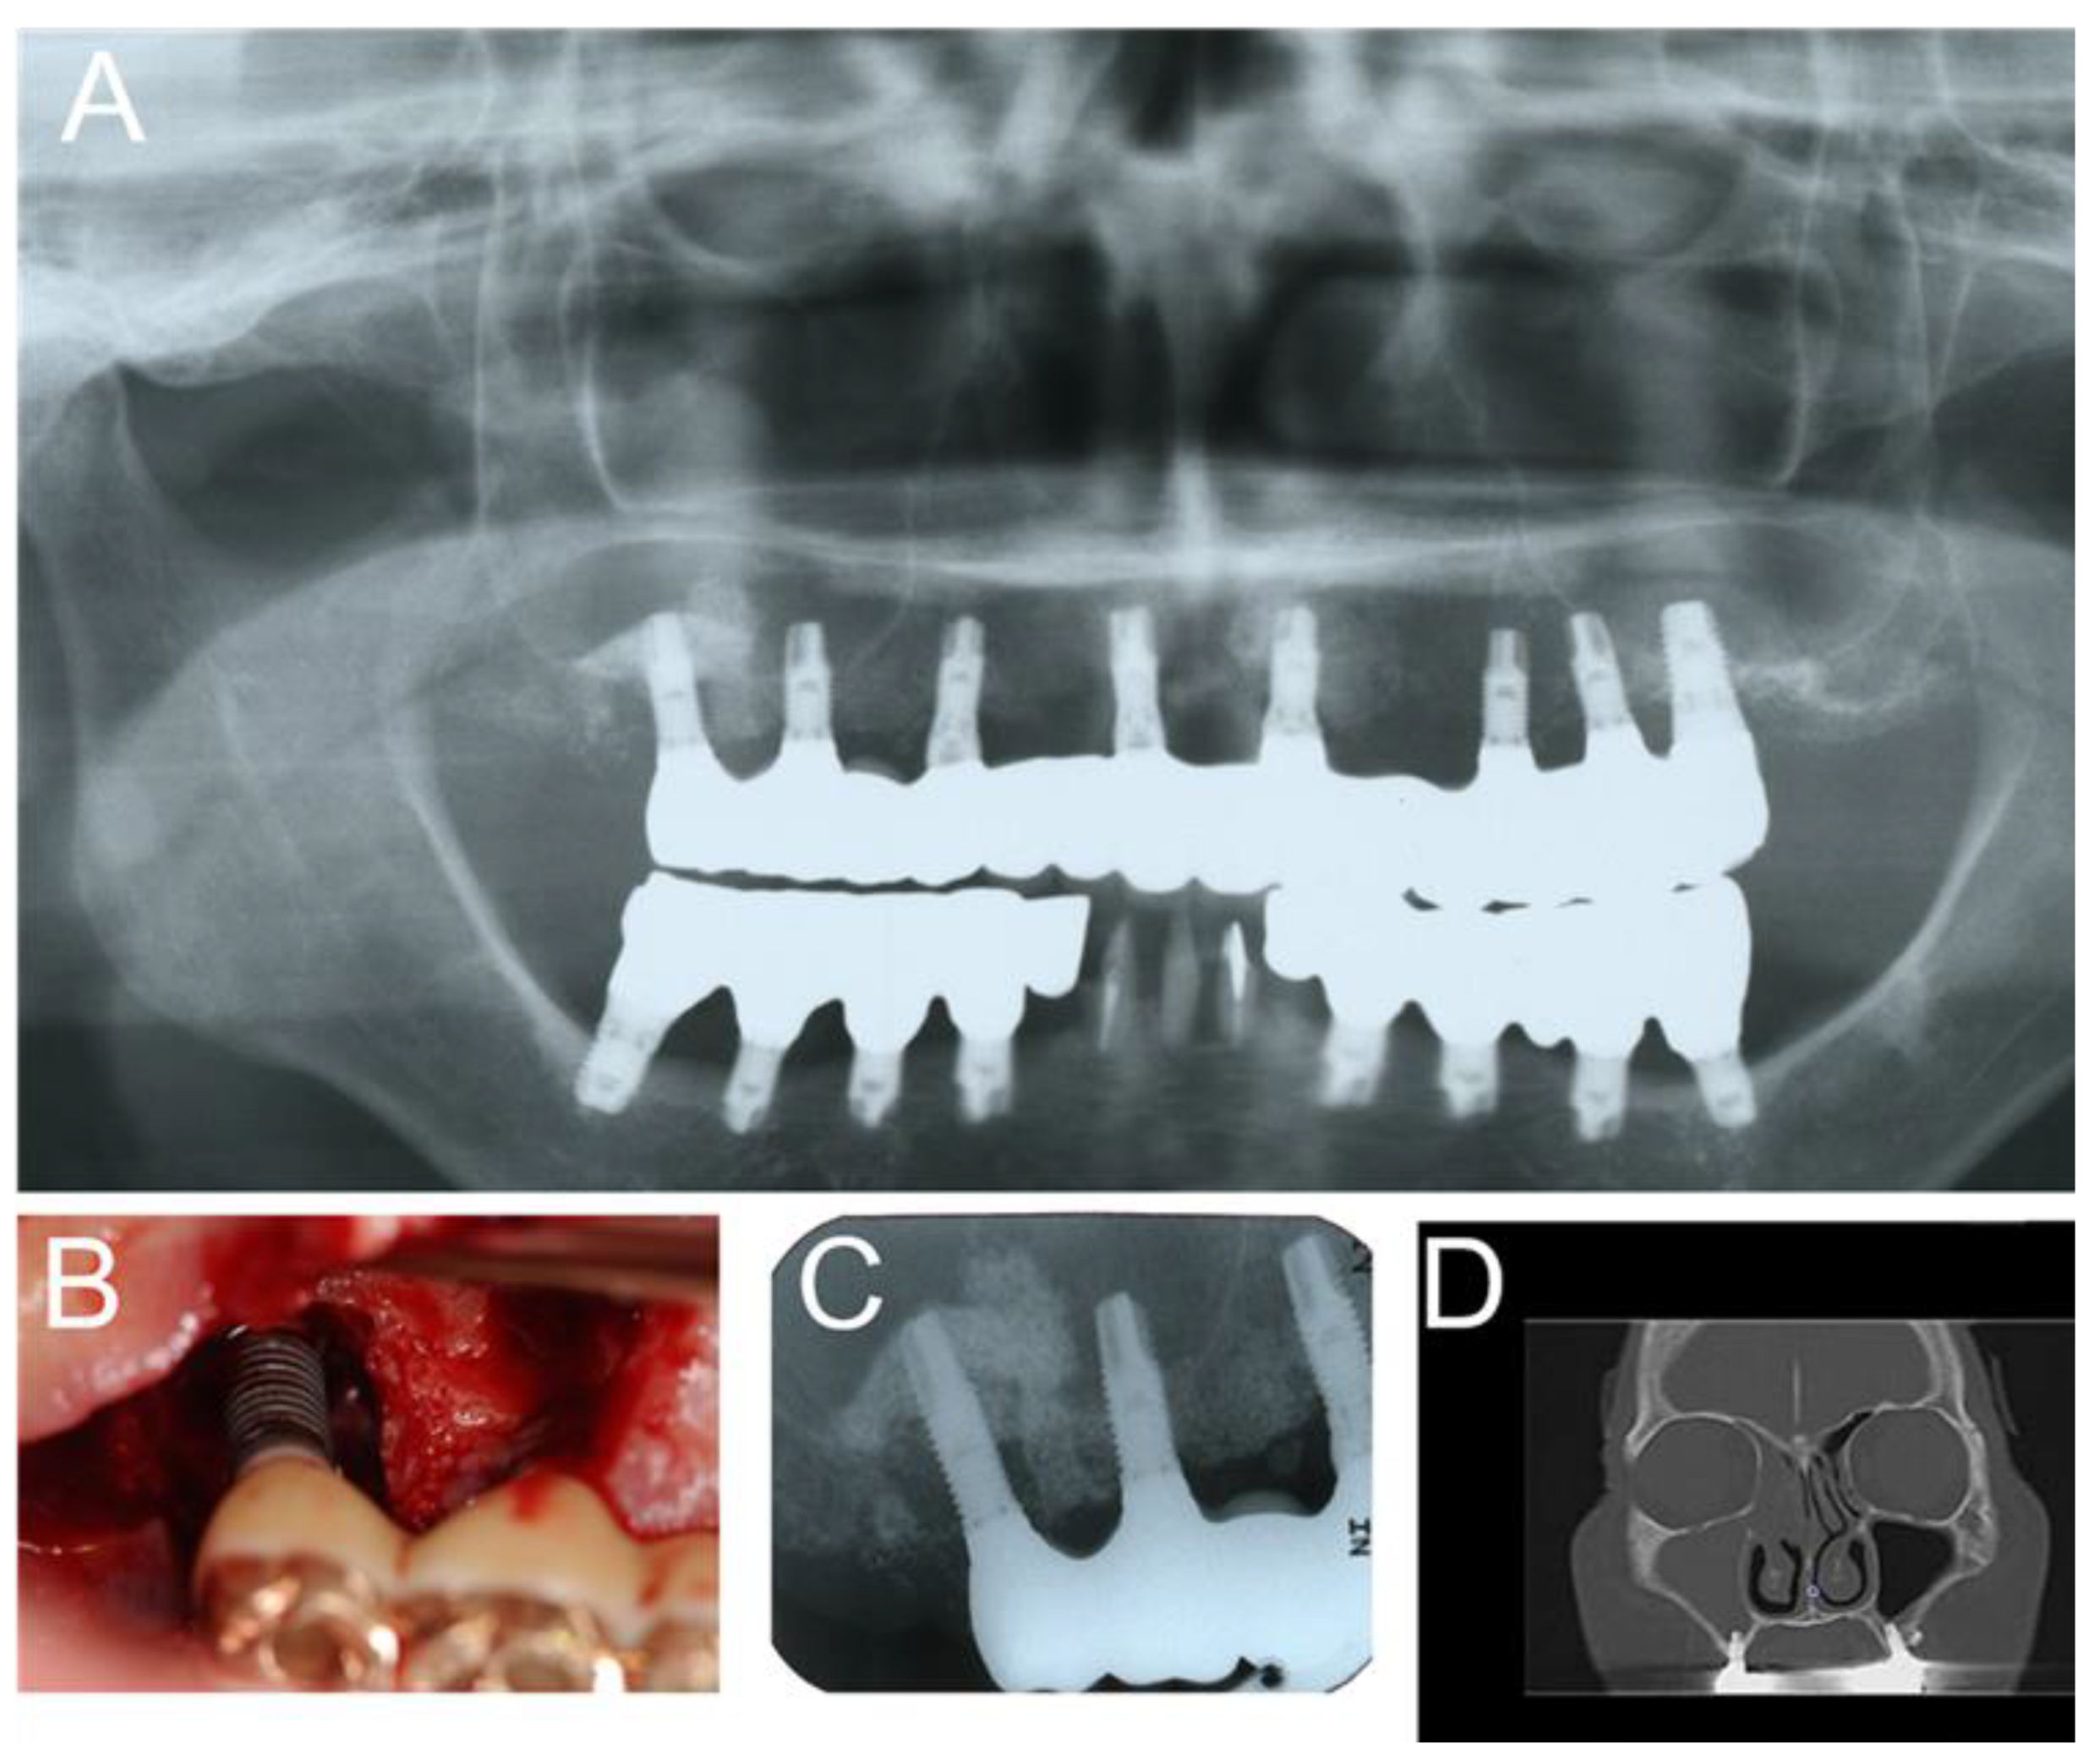

Figure 2.

(A) During implant placement, the surgeon pierced the maxillary sinus mucosa, and the postoperative panoramic photograph shows that the implant body slightly protrudes into the left maxillary sinus floor; (B) 7 days after the operation, the upper left maxillary sinus was opaque, suggesting acute left maxillary sinusitis. (unpublished data).

The possible causes of chronic maxillary sinusitis after dental implantation caused by surgeons include sinus penetration by the implant (Figure 2), perforation of the Schneiderian membrane during the sinus lift, and so on [3]. However, maxillary sinusitis rarely occurs after sinus penetration by implant or perforation of the Schneiderian membrane during a sinus lift, because the implant body or bone graft is sterilized and clean [8]. Therefore, it is not clear whether sinus penetration by the implant or perforation of the Schneiderian membrane during a sinus lift is a possible factor predisposing the patient to maxillary sinusitis after dental implantation.